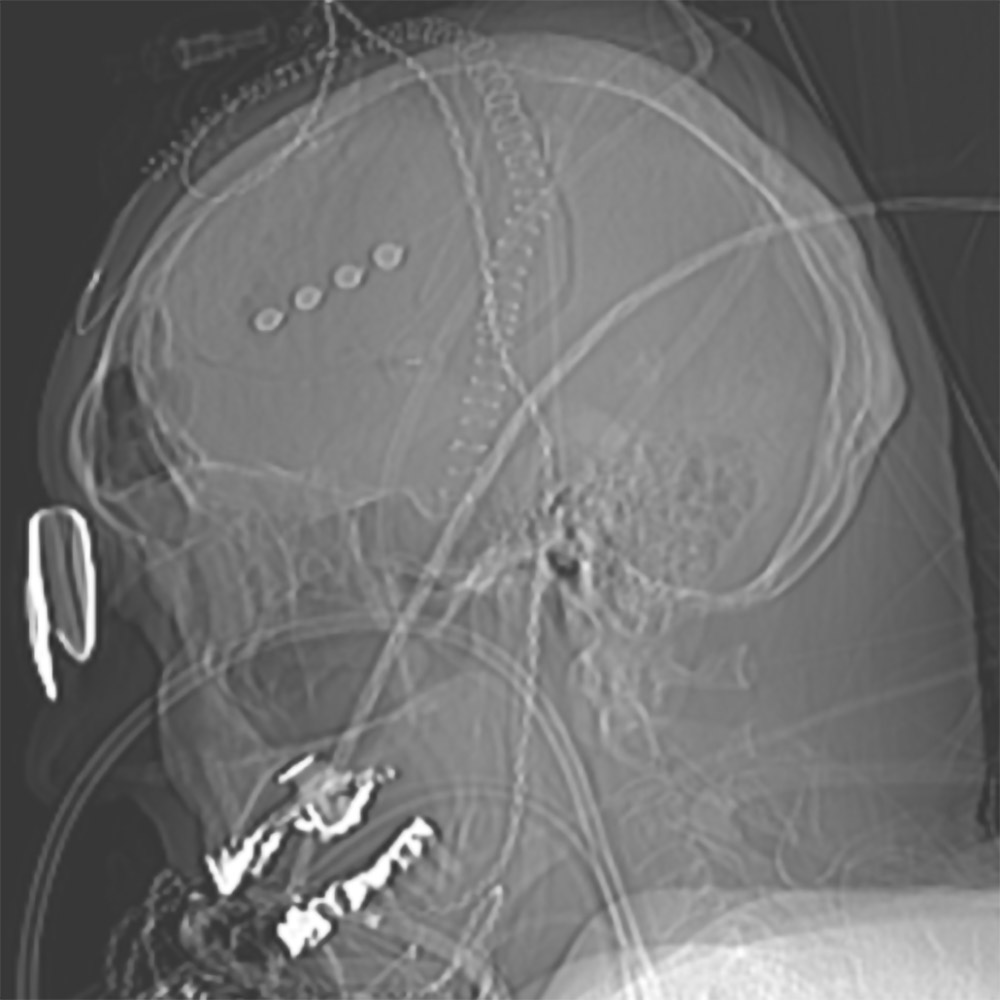

Seitliche Schädelaufnahme eines Patienten mit subduralem Hämatom

und auf dem Hirn aufgelegter 4-Kontakt-EEG-Elektrode (vier Punkte),

mit der Anfälle detektiert werden können (1). © Prof. Dr. Adam Strzelczyk

Auch PatientInnen mit akutem subduralem Hämatom (Blutung unter der Hirnhaut) erleiden häufig Krampfanfälle. Im Rahmen von Studien wird bei ihnen ein Dauer-EEG abgeleitet. Dafür erhalten sie EEG-Elektroden unter die Kopfhaut implantiert (siehe Bild). „Auch hier verfolgen wir die Fragestellung: Kann diese Datenanalyse mit künstlicher Intelligenz vorhersagen, ob und wann Anfälle auftreten? Falls ja, könnten wir rechtzeitig intervenieren und damit die Personen vor weiteren Verschlechterungen des Zustands schützen und präventiv behandeln?“, erklärt Professor Rosenow. Solche therapeutischen Ansätze basieren in der Regel auf Voruntersuchungen in Tiermodellen.